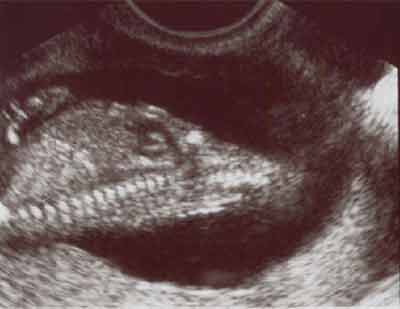

Aorte

Artère pulmonaire